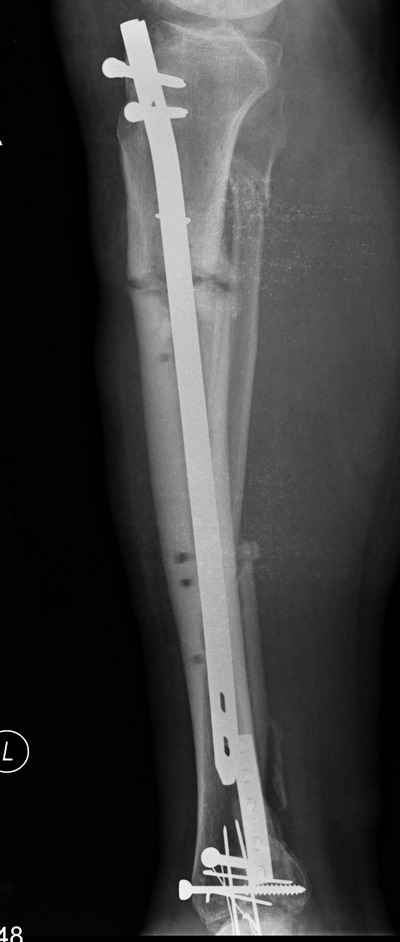

Открытый перелом- пхо+стержневой аппарат-штифтование. Через 4 месяца отек, температура 39….

Удален штифт-резекция+билокальный остеосинтез. Выращивание дистракционного регенерата

Повторное штифтование с рассверливанием. Оставлен дистально «легкий» аппарат для создания компрессии сближенных опилов на 4 недели.

Итак - удалили стержень, воспалительный процесс к тому моменту купирован, наложили кастовую повязку и в течение 3 месяцев на контрольных рентгенограммах - признаки консолидации. Уже в сентябре, т.е черз 5 месяцев после нагноения пациент вернувшиь с подвождной охоты привез здорового сазана - основная жалоба - ноги побаливают после длительного лпаваня в ластах. Прилагаю снимки через год после удаления стержня. Вот такая, на этот раз счастливая казуистика.